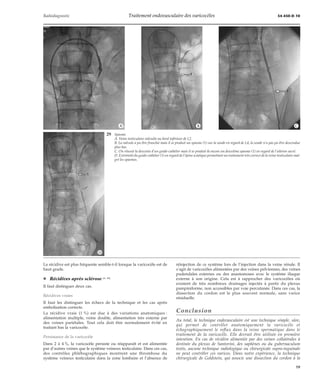

RÉCIDIVES [68]

¦ Récidives postchirurgicales

Après une chirurgie de type Ivanissevich (ligature haute au niveau

de l’aileron sacré du système veineux testiculaire) [40, 47, 63, 68], les

récidives sont classiques, de l’ordre de 6 à 9% (dans les meilleures

mains), dues à la distension des collatérales réopacifiant en dessous

de la ligature la zone sous-jacente du système veineux testiculaire.

Cela est très bien vu en phlébographie et parfaitement accessible à

la technique endovasculaire (fig 40, 41, 42).

40 Aspect postopératoire et récidives. Suspicion de récidive postopératoire.

A. L’injection dans la veine rénale ne montre pas de reflux vers le sys-tème

veineux testiculaire. 1 : anastomose veine cave inférieure.

B. Son cathétérisme a cependant été réalisé et l’on constate une veine

testiculaire de petite taille parfaitement ligaturée en regard de la sacro-iliaque

(1).

La varicocèle est peut-être alimentée par des veines superficielles ou pel-viennes.

41 Aspect postopératoire et récidives.

Récidive après traitement chirurgical, les clips (1) sont visibles en regard de l’aileron sacré.

Une collatérale dilatée (2) réinjecte le tronc testiculaire un peu au-dessus de l’épine sciati-que.

La sclérose est facilement réalisée.